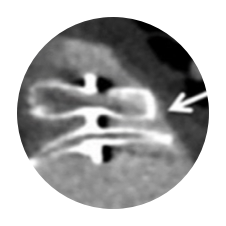

SEAL FLX

Study Design

- Single-center, retrospective study of LAAO implantation at Aarhus

University Hospital (Denmark) between 2018-2020.

1st cohort: Amplatzer Amulet (n=150) 2018 – 2019

2nd cohort: WATCHMAN FLX (n=150) 2019 – 2020 - Cardiac CT was performed 8 weeks after LAAO

WATCHMAN FLX Demonstrated Statistically Superior Complete Occlusion** vs Amulet (p=0.001)

**Complete LAA occlusion defined as no visible peri-device leak (PDL) and absence of contrast patency in the distal LAA (LAA/left atrium Hounsfield ratio <0.25)